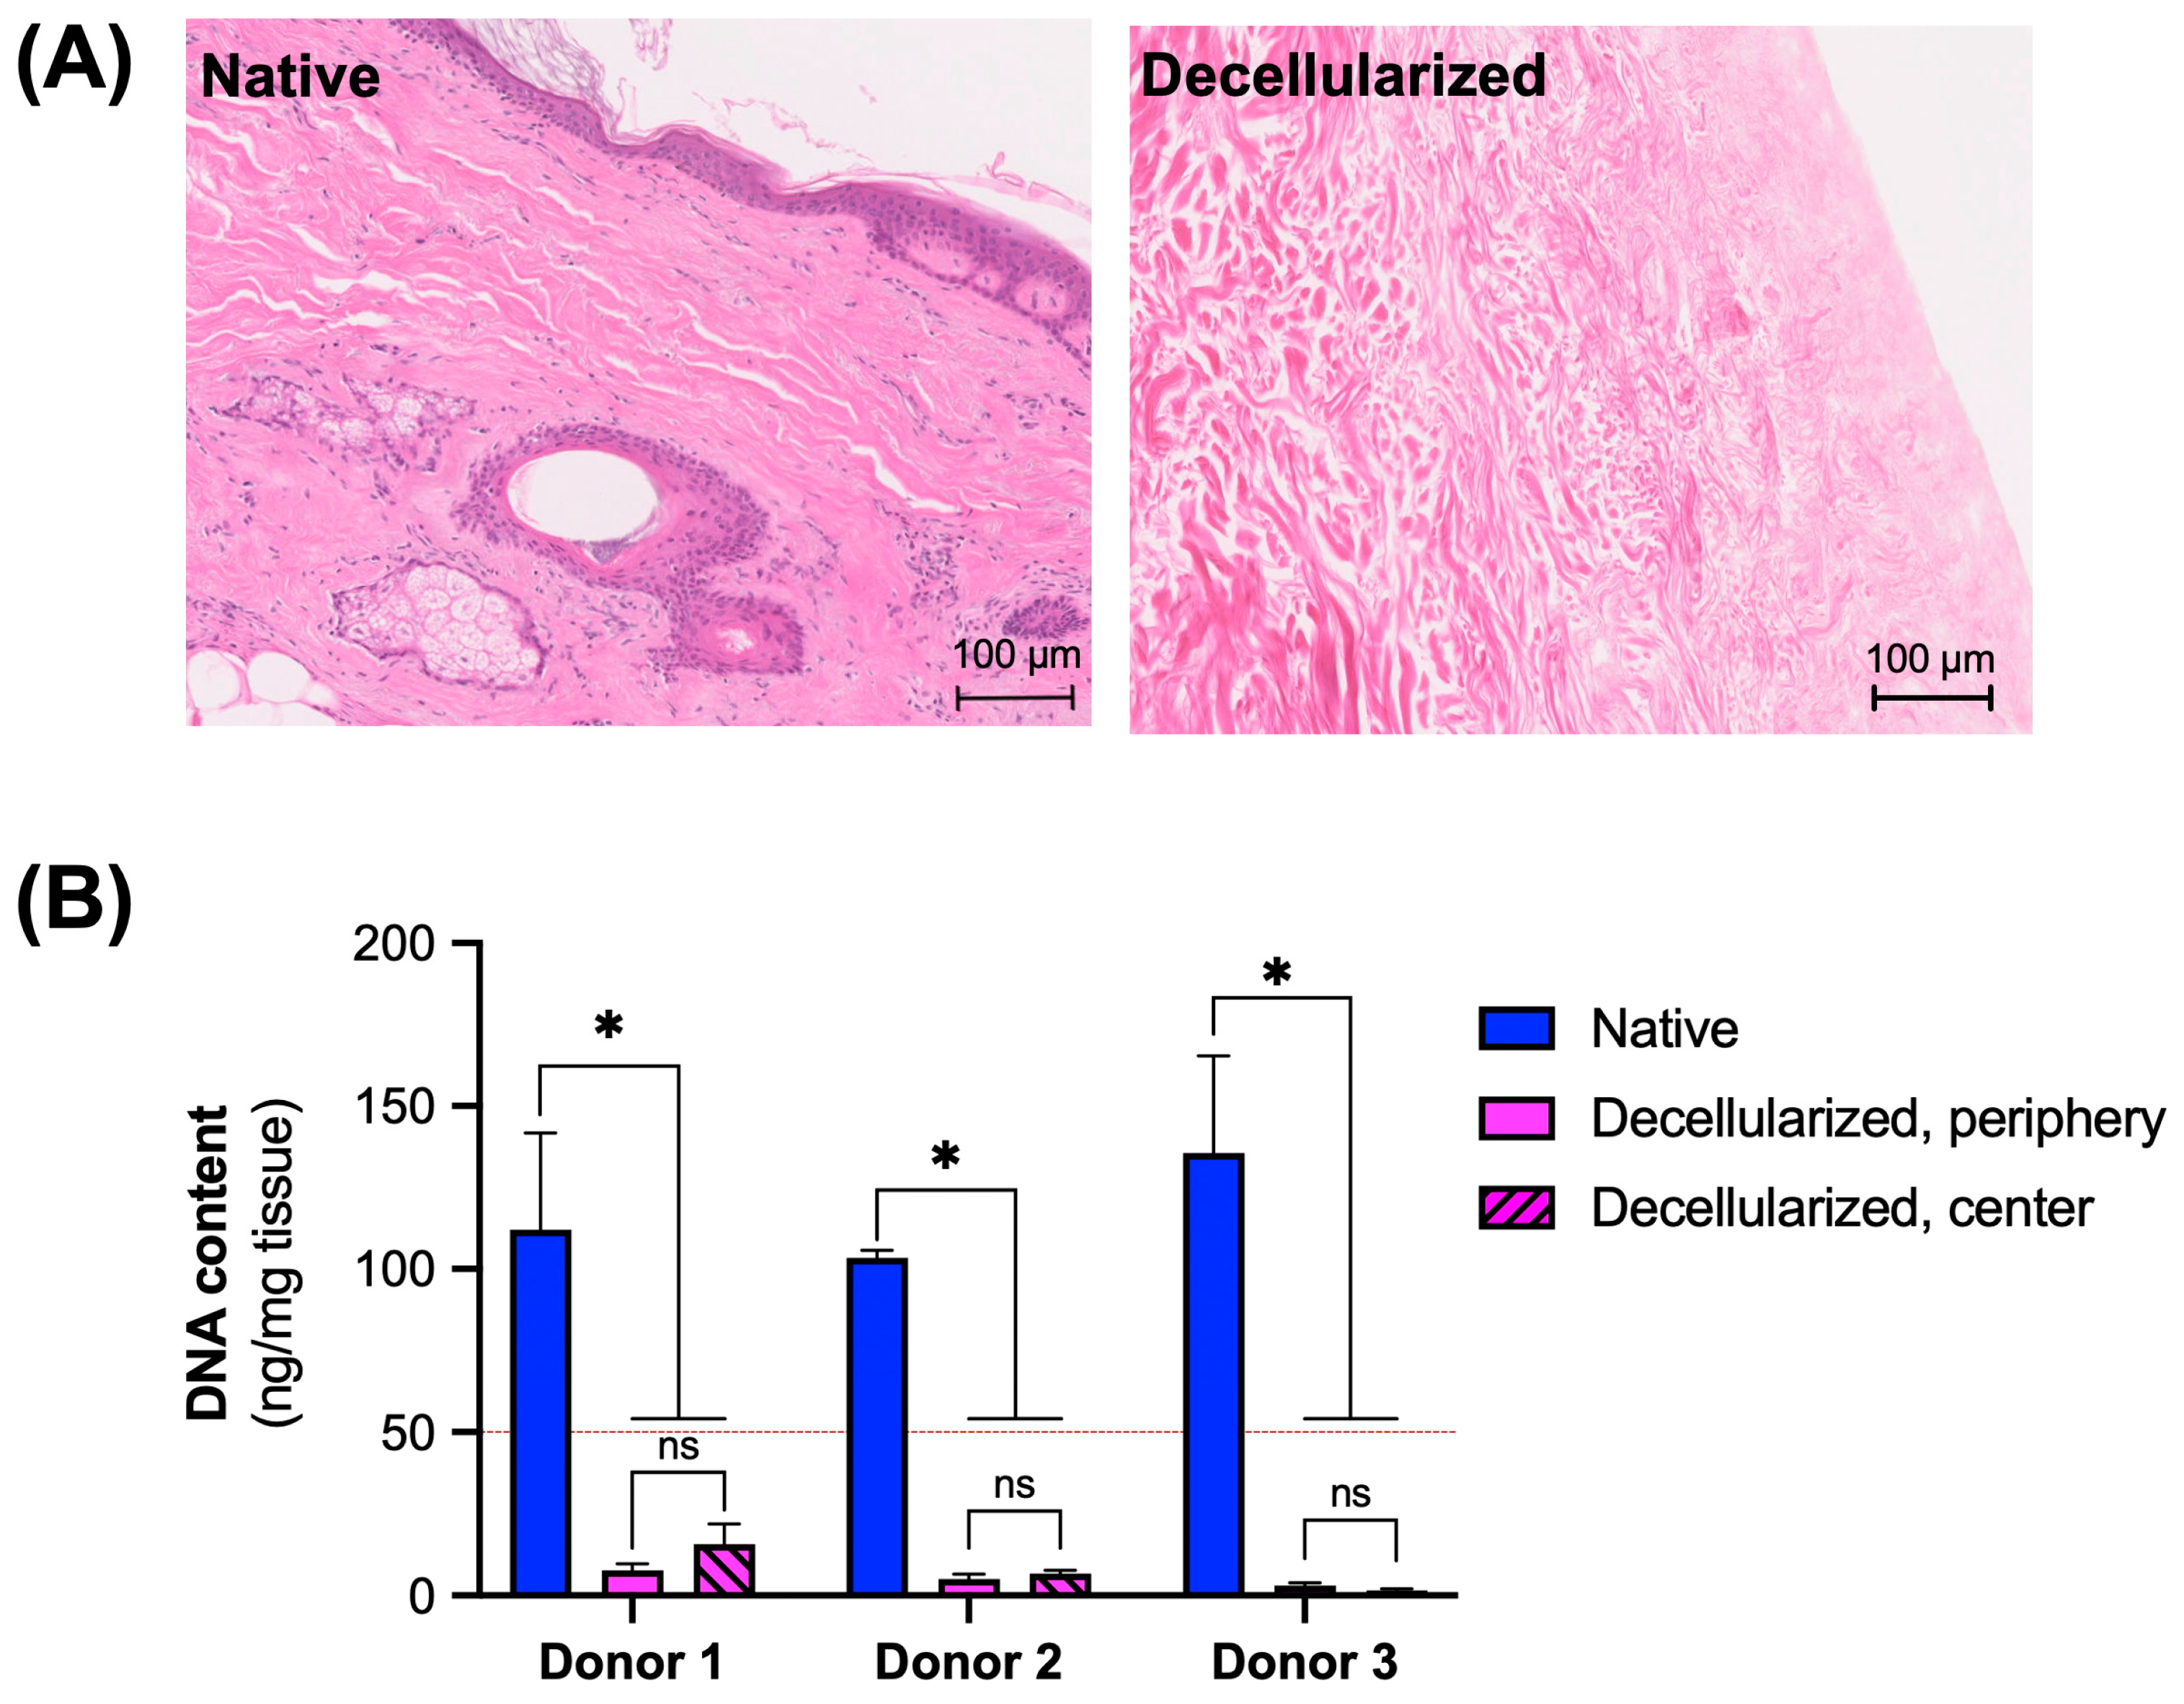

3.1. Assessment of Decellularization Efficiency